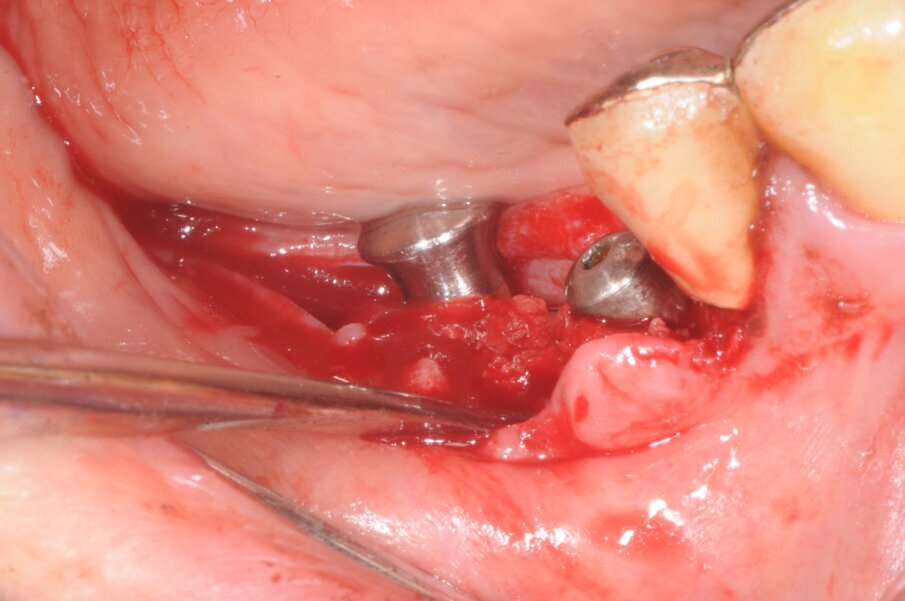

Chirurgia

La terapia anticoagulante non è stata interrotta prima della chirurgia ed è stata somministrata la profilassi antibiotica come da protocollo. È stata eseguita un’incisione crestale senza tagli di scarico che è stata estese distalmente fino al trigono retromolare per esporre la branca mandibolare ed avere un sito per raccogliere osso autologo con una fresa carotatrice. Sono state eseguite le osteotomie a basso numero di giri come da protocollo BTI per ottenere un’ulteriore quantità di osso autologo raccolto dalle frese e inseriti due impianti BTI Core 3,75 x 4,5 e 3,5 x 6,5 rispettivamente in posizione 46 e 45.

L’osso autologo è stato mescolato con gel piastrino ottenuto da centrifugazione del sangue del paziente mediante metodica Endoret BTI. La membrana ottenuta è stata applicata a protezione della corticale vestibolare. Ulteriori membrane di gel piastrino sono state applicate sopra l’osso autologo. La stabilita primaria di entrambi gli impianti era superiore ai 50 Newton per cui sono stati avvitati i pilastri Multi-Im e i pilastri di guarigione per un tecnica con una sola chirurgia. Sono state applicate suture sintetiche non riassorbibili a punti staccati (Figg. 3–10). Successivamente è stata eseguita una Rx di controllo. Le suture sono state rimosse a due settimane e la paziente riferì di avere avuto disagi minimi, senza ematomi o edemi estesi e scarsa dolenzia che non richiese l’assunzione di antinfiammatori.